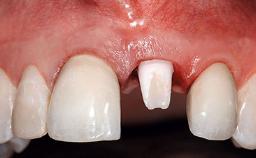

Replacement of an Ankylosed Upper Left Central Incisor: Bone Augmentation and Socket Grafting, Late Placement of an RC Bone Level Implant

Prosthesis Type FDP

SAC Level Advanced

Defining Characteristics One missing tooth to be replaced by an implant-borne crown

Loading Protocol Conventional or early